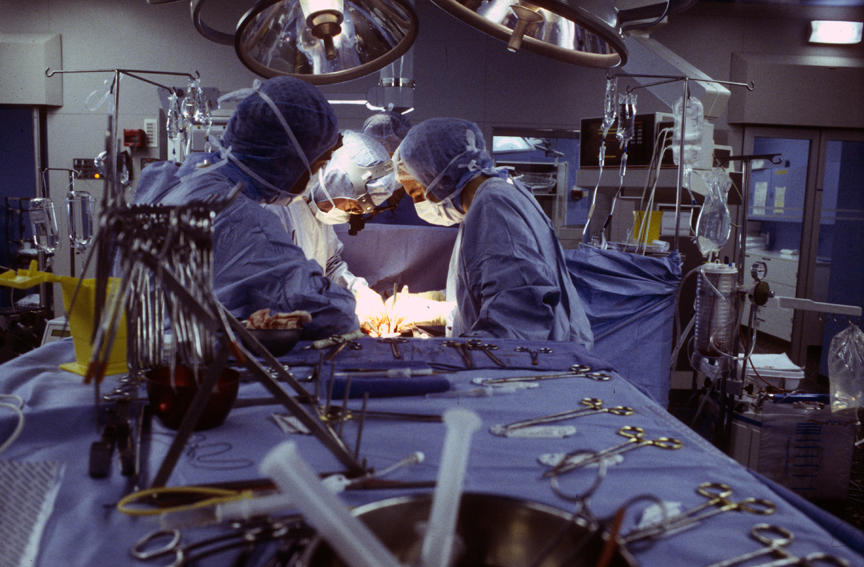

Soy Médico Especialista En Ortopedia y Traumatología

Con mas de 350 cirugías anuales me permite tener una experiencia importante en tomar la mejor decisión quirúrgica si fuese necesaria para su tratamiento.